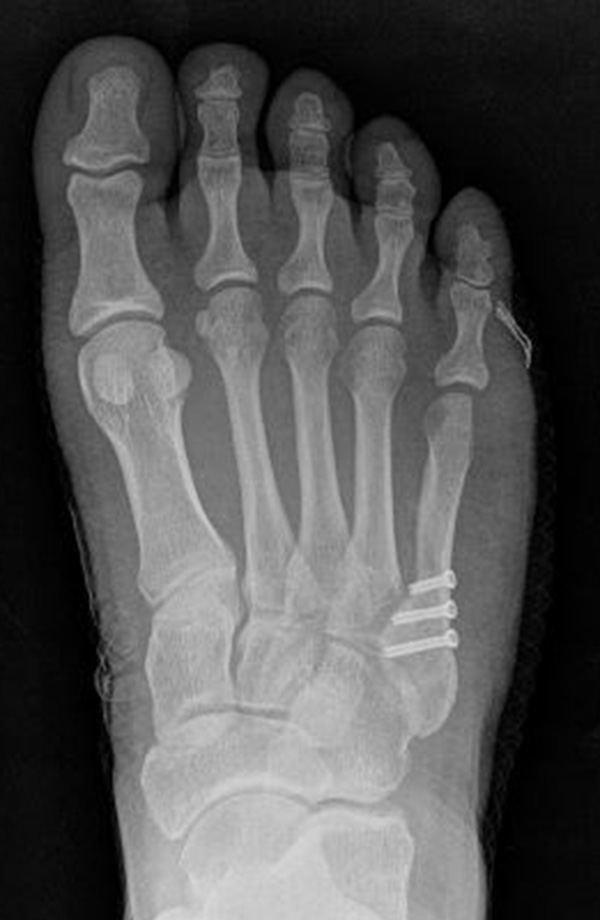

Abb. 3a, b: Präoperatives (a) und postoperatives (b) Röntgenbild bei Korrektur einer Typ I Deformität durch eine Exostosenabtragung.

Abb. 12a: Typ III Deformität präoperativ im belasteten dp Röntgenbild.

Abb. 12b: Dorsoplantare Röntgenkontrolle nach medial schließender Osteotomie mit Schraubenosteosynthese.

Abb. 12c: Schrägaufnahme nach medial schließender Osteotomie mit Schraubenosteosynthese.

Abb. 12d: Seitliche Aufnahme nach medial schließender Osteotomie mit Schraubenosteosynthese.